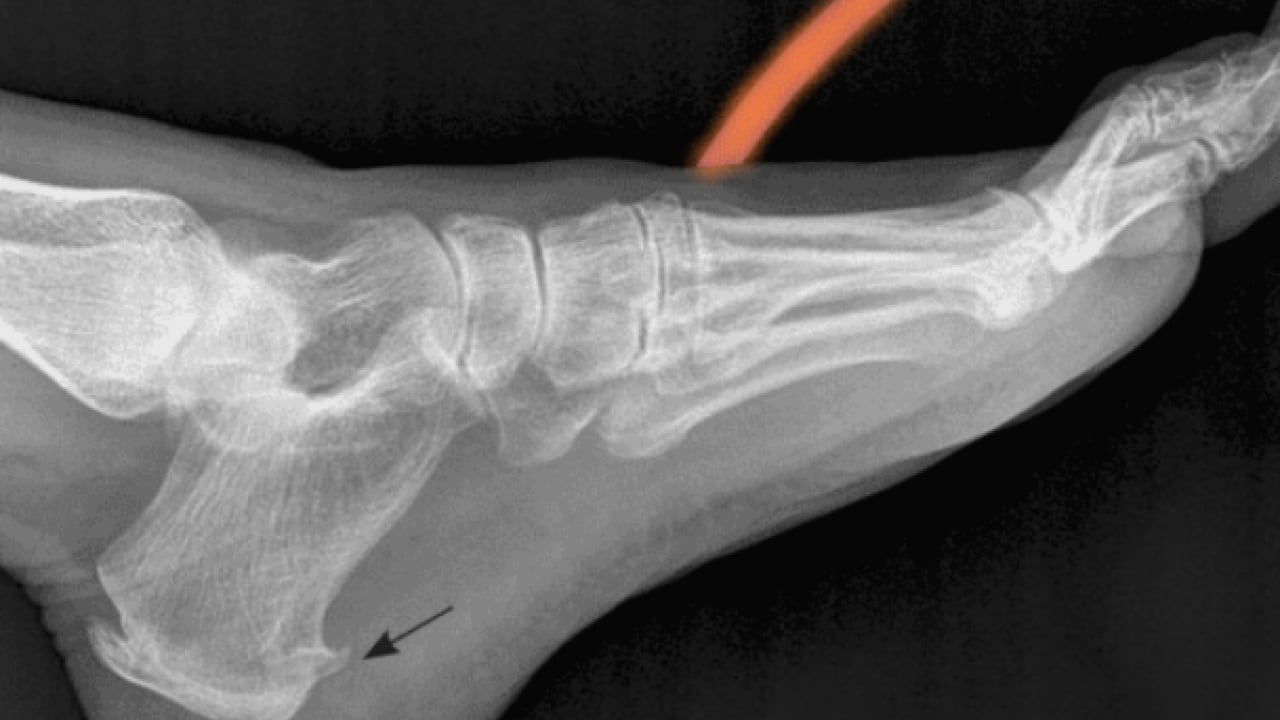

"Bu noktada, iltihabın doğrudan hedef alındığı anjiyografik bir yöntem geliştirdik. Bacak atardamarından ilerleyerek topuk bölgesindeki hedef damarlara ulaşıyor ve iltihap kurutucu ilacı doğrudan sorunlu alana veriyoruz.

İşlem öncesi MR ve anjiyografiyle iltihabı net şekilde görebiliyoruz.

Tedavi sonrası hastalarımızda ağrı düzeyinin 7-8'lerden 1-2 seviyelerine düştüğünü gözlemledik ve takiplerimizde nüksle karşılaşmadık. Topuk ağrısı hafife alınmaması gerekir. Ağrı uzun süre devam ediyorsa mutlaka uzman değerlendirmesi yapılmalı. Kişiye uygun tedavi planı belirlenmesini öneriyoruz."